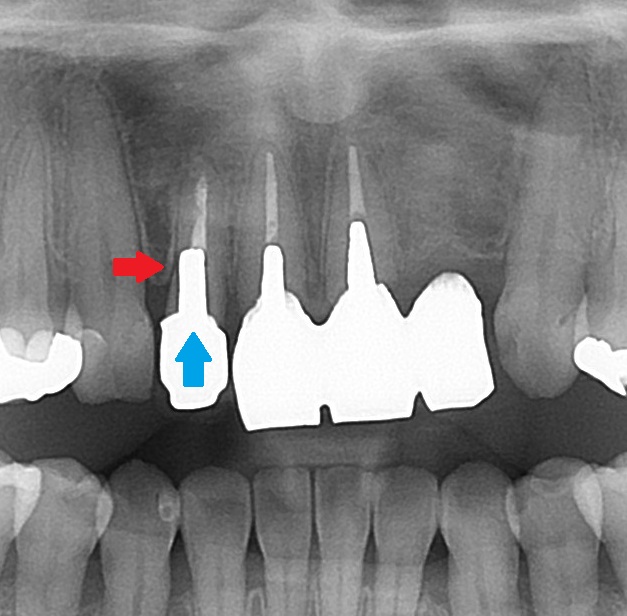

エックス線検査(レントゲン)で歯の中の状態を見てみると、

このような状態でした。

こちらの歯、3本が差し歯になっており、

後でお話しますが、メタルコアが入っています。

こちらの1本は歯が無く、ダミーの歯で繋がれています。昔に事故で抜いてしまったようです。

CT検査では、根の先に炎症などのトラブルはありませんでした。

エックス線を見てみると

こちらの矢印の歯のコアが、太く、適正な方向に入っていないためです。方向がそれています。

斜めに埋め込まれてしまっており、赤い矢印の部分の歯の残量が無いためです。既に穴が開いているかもしれません。

このコアを外す際に、赤い矢印の箇所に穴が開くか、割れる可能性があります。

現在、歯に症状が無いために、このまま現状を維持することを患者さんと相談しました。